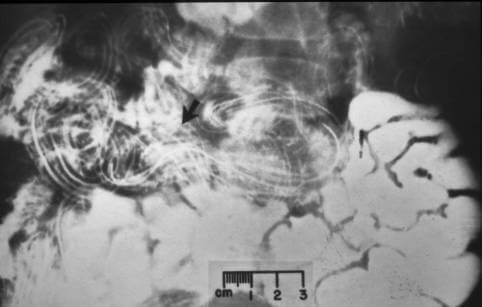

U sredini fotografije: melanom uzrokovan parazitima.

“Imamo arhivu fotografija: fotografije snimljene tokom obdukcije kada otkrijemo različite parazite u organima tijela. Evo nekoliko primjera. Ali upozoravam vas, oni su užasni. »